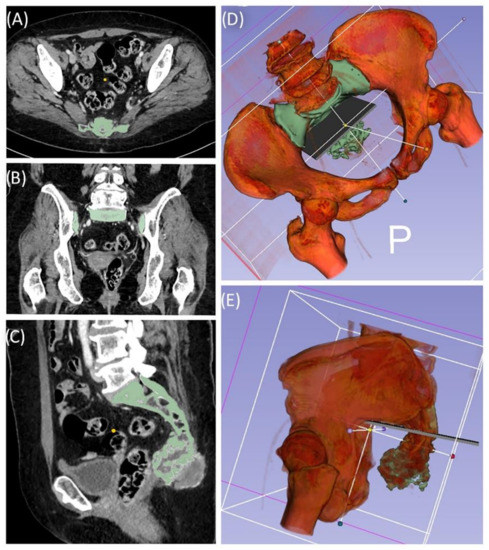

Case 1 involved a 22-year-old female patient suffering from a multiple cartilaginous exostosis disease with a secondary peripheral chondrosarcoma G3 of the right ilium without metastasis. The resection was performed as navigated internal hemipelvectomy (P1a), followed by augmentation of the right ileum with a standard screw-rod system (Expedium, DePuy Synthes Spine Inc., Raynham, MA, USA) and revision cement (COPAL® G+C, Heraeus, Wehrheim, Germany) (Figure 2). This procedure allowed preservation of the hip joint. Trochanter resection was followed by reconstruction of the ventral hip joint capsule and reinsertion of the musculature using an attachment tube (Implantcast, Buxtehude, Germany). During treatment, superficial dry skin necrosis at the Enneking approach site occurred without signs of infection and eventually healed. The first follow-up 3 months after surgery showed a stable and increasingly fluid gait pattern with a positive Trendelenburg sign. The range of motion of the right hip joint was fully preserved. At the 15-month follow-up, the patient was free of pain and was able to walk a three-kilometer distance. The native X-ray and MRI of the pelvis showed no signs of tumor recurrence.

Figure 2. Case 1: Preoperative planning and segmentation of tumor volume components [bony (pink) and soft tissue (teal)] (A); resection planes [transverse (orange) and axial (blue)] during surgery with navigated chisel (orange) (BE) intraoperative situs during resection (F); postoperative radiograph with reconstructed iliac defect (G).